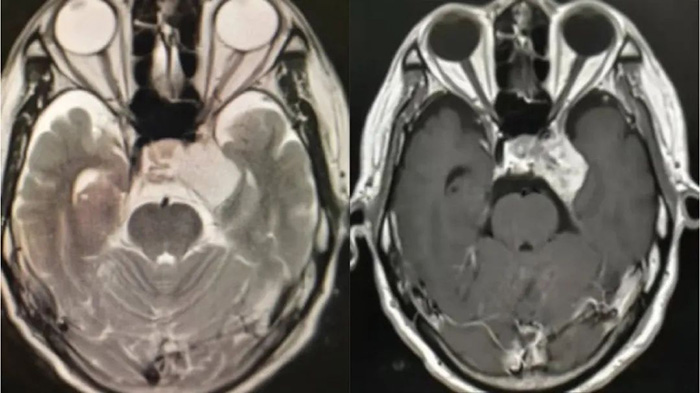

Case 1, a 26 year old male patient, was diagnosed with cerebral arteriovenous malformation due to epilepsy in 2018 and underwent interventional embolization treatment. Due to ongoing seizures, I came to our hospital from April 2021 to request gamma knife treatment. Figure A-C

Figure A: 2021-04-26 First gamma knife treatment

Figure B: 2021-11-03 Second Gamma Knife Treatment

Figure C: On February 22, 2023, magnetic resonance imaging showed a significant reduction in abnormal vascular clusters and no seizures.